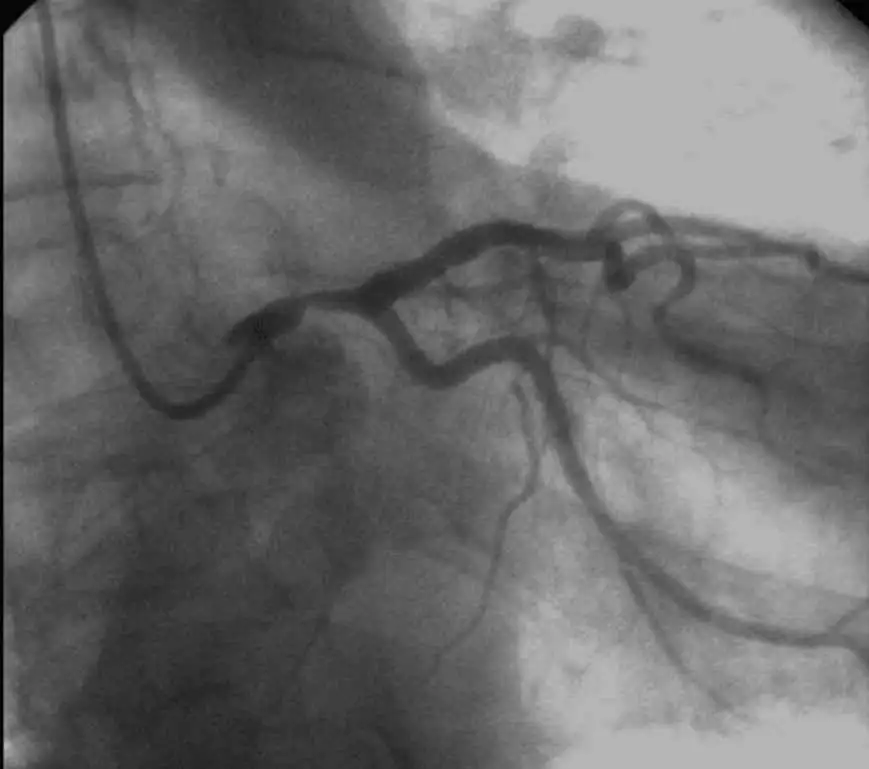

ST-elevation of greater than 1mm in aVR indicates triple vessel coronary disease, left main trunk disease, or proximal LAD disease. If that ST-elevation is greater than the ST-elevation in V1, it differentiates between left main trunk and LAD disease. The treatment for anyone with these conditions is almost always coronary artery bypass grafting. This patient needs to be taken to the cardiac catheterization laboratory to obtain images for use in interventional surgery. An ECG without ST elevation in aVR almost certainly rules out the presence of significant left main trunk disease. The following angiogram shows the gravity of this type of lesion clearly.